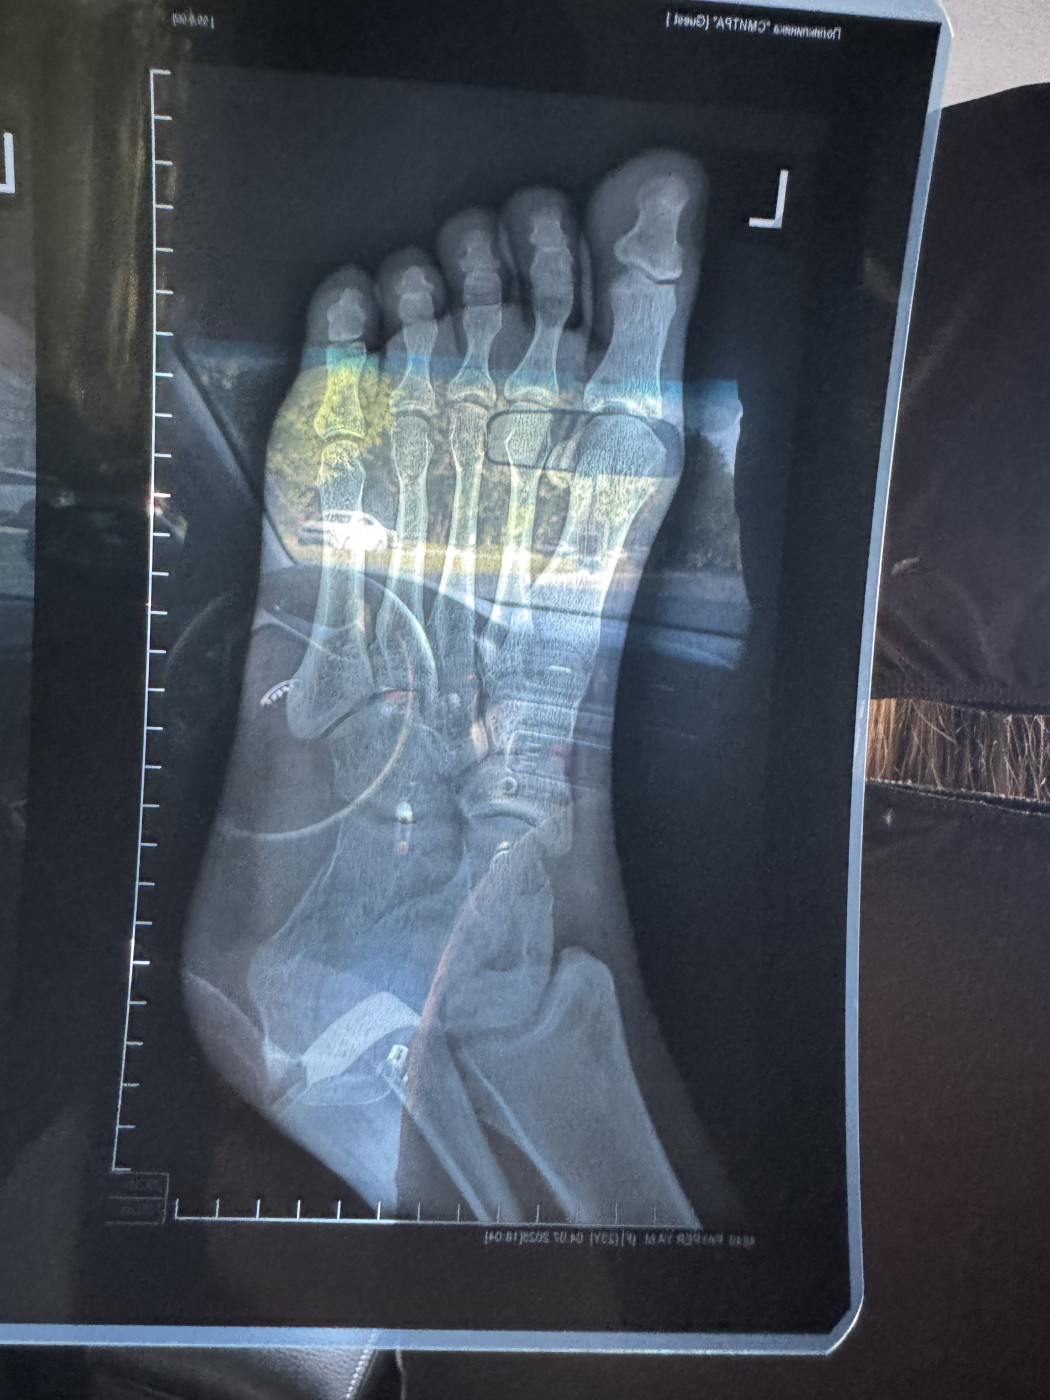

Перелом ноги   1 ответ

Здравствуйте. Диагноз: Закрытый перелом медиальной лодыжки со смещением отломков, перелом н/3

малоберцовой кости с незначительным смещением отломков и разрывом дистального

межберцового синдесмоза. Закрытый перелом заднего края большеберцовой кости без смещения в левом голеностопном суставе. Проведена операция. Какие последствия перелома и сроки восстановления? Особенно смещение малоберцовой кости которое осталось без изменений

26 июл 2025 11:55